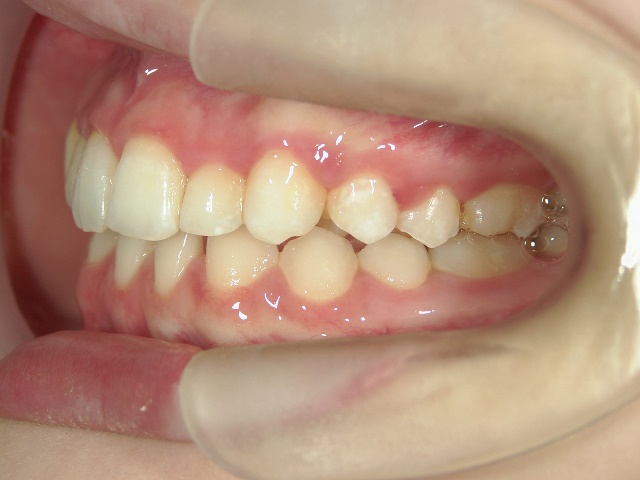

矯正歯科 治療前 右

矯正歯科 治療前 左